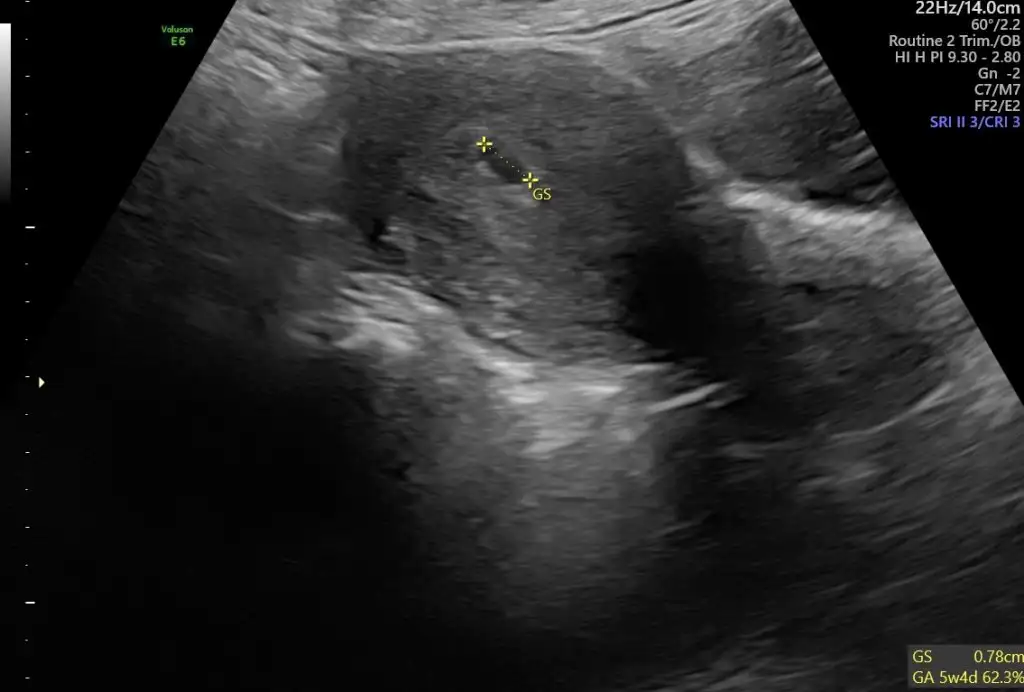

Bana da tahminde bulunabilir misiniz lütfen ☺️

Bende merak ediyorum 6 haftalık karından çekildi 🥰